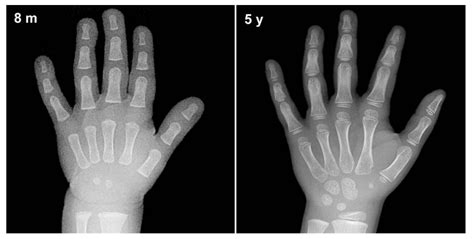

A Bone Age X-ray is a brief, painless imaging procedure that captures a single X-ray image of the left hand and wrist. This specific area is chosen because it contains numerous small bones that develop and change in a predictable sequence throughout childhood and adolescence. As a child grows, the cartilage within these bones gradually hardens, a process known as ossification. Radiologists analyze these changes to estimate the "skeletal age" of the child.

4. Analysis: A pediatric radiologist will review the image, comparing the development of the hand bones to standardized sets of X-rays known as the Greulich and Pyle atlas or the Tanner-Whitehouse method.

When the radiologist analyzes the Bone Age X-ray, they are looking specifically at the epiphyseal plates, often called growth plates. These are the areas of cartilage at the ends of the long bones. As a child approaches the end of their growth spurt, these plates harden and fuse together. Once they are fully fused, bone growth stops. The following table summarizes how skeletal age comparisons are typically interpreted by physicians.